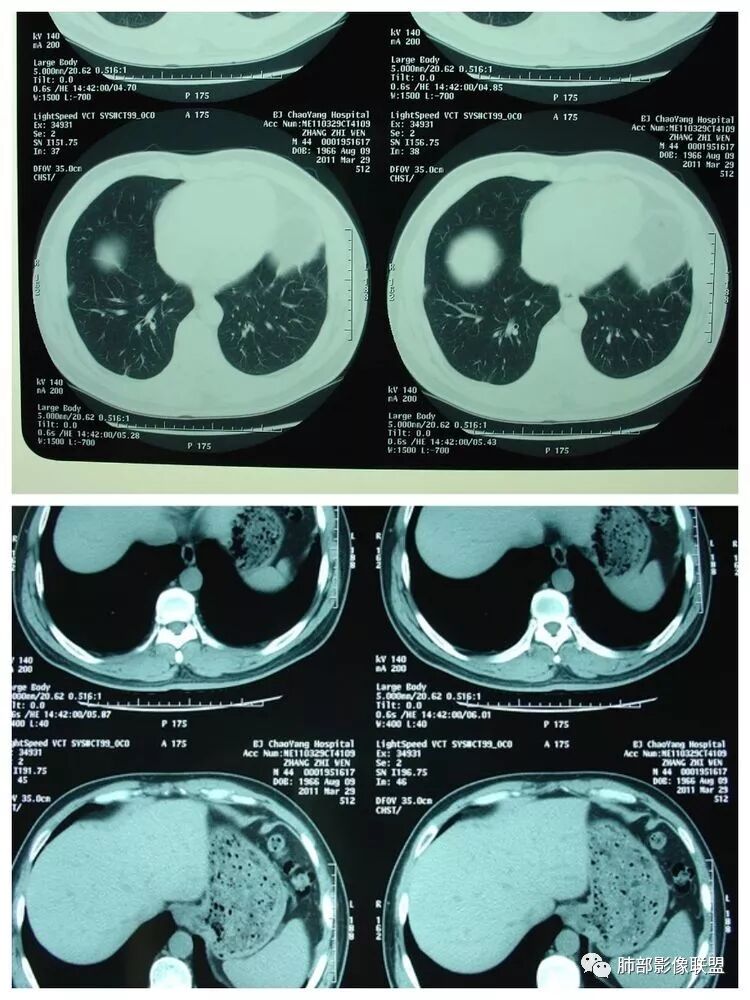

脾大,肝内结节中央似有点状血管通过,炎性可能

但不是典型的脓肿南边:综合临床,影像,肺部是血道来源感染,肺克雷伯杆菌肺炎放前面。毛霉菌待排吧没意见:低蛋白、ALT异常可能间接提示肝脏问题go and see:这个肝脓肿确实不够典型多少。初学者:

2.本例应当属另一经典感染途径,肝脏感染,双肺脓毒性肺炎。大家都注意到患者的基础疾病,糖尿病。

4.本例肝脏的病灶并未出现典型肝脓肿图像特征,病灶密度及中央血管样结构显然不符合一般的囊肿。应当说,它是感染灶,但并未液化形成脓腔。